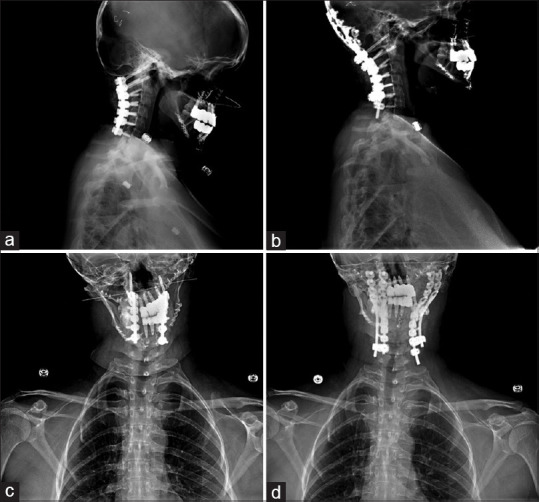

Instability of the occipitocervical junction may compress neural elements, resulting in progressive disability. After the Kickstand Rod technique was developed to correct for thoracolumbar scoliosis, the Candy Cane construct was developed for chin-on-chest deformity at the cervicothoracic junction as a similar three-rod approach. Demonstrated is a four-rod iteration utilized to stabilize the occipitocervical junction and correct condylar instability, termed the Catcher's Mitt technique. A 34-year-old woman with Goldenhar syndrome, hemihypertrophy, and a complex neurosurgical history including Chiari decompression, clival chordoma resection, and a previous cervical fusion presented with quadriparesis, dysphagia, and bilateral upper extremity paresthesias. She was found to have pontomedullary and craniocervical instability with occipital translation and subluxation of the atlantooccipital joint, contributing to her neurological decline. A single midline incision and periosteal dissection exposed her prior O to C6 instrumented fusion. Existing rods were replaced, and a third plate-rod was placed on the right from O to C6. On the left, a fourth plate rod was positioned from C1 to C6. Four top-loading connectors secured the accessory rods to the primary construct. After confirming a stable lordotic alignment, distraction across the accessory rods was used to assist with coronal correction. The Catcher's Mitt construct improved this patient's sagittal and coronal plane deformity. Postoperatively, the cervical sagittal vertical axis improved by 25 mm and the chin-brow angle by 20 mm. Significant improvements in functional status were achieved at 2-year follow-up. A one-stage posterior approach with construct augmentation using third and fourth accessory rods can correct atlantooccipital subluxation following failed occipitocervical fusion.